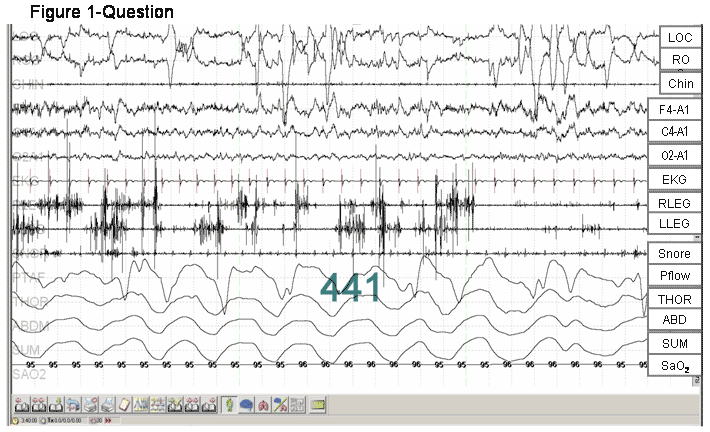

Discussion: By definition, REM sleep is characterized by low voltage mixed frequency EEG, rapid eye movements, and skeletal muscle atonia (figure 2, blue arrows show muscle atonia of chin and anterior tibialis EMG). However, in the PSG fragment shown (figure 1-answer), the 30 second epoch shows absence of REM atonia (loss of normal skeletal muscle atonia) as depicted by excessive phasic increases (red arrows) in the anterior tibialis EMG, occupying at least 50% of the duration of the epoch of REM sleep.

This patient had a history of acting out his dreams, as well as typical PSG findings of RBD. This particular fragment best illustrates the excessively increased phasic activity in limb EMG but without any sustained tonic activity in chin EMG.